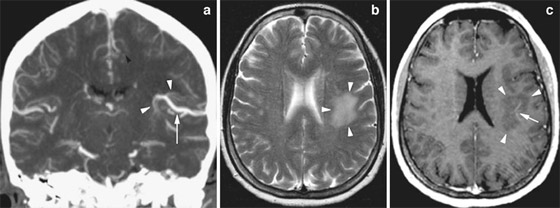

وأوضح الأطباء أن ما حدث كان بسبب تناول الرجل لحم الخنزير المقدد غير المطبوخ جيدًا، وفقا لما ذكرت شبكة بريطانية، حيث كشف تصوير بالأشعة المقطعية أجراه أطباء لدماغ الرجل، عن بيوض الدودة الشريطية، كما تم تشخيص المريض بداء الكيسات المذنَّبة العصبي.

يشار إلى أن هذا الداء يعدّ نوعاً خاصاً من داء الكيسات المذنبة، ويحدث بسبب عدوى بالشريطية الوحيدة، وهي شريطية حقيقية (Eucestoda) تُوجد في الخنازير، والتي يمكن أن تصل إلى الأنسجة مثل العضلات والدماغ. في حين نفى المريض تناول طعام نيء أو وجبات من الشارع، إلا أنه اعترف بعادة تناول لحم الخنزير المقدد المطبوخ بشكل خفيف وغير المقرمش معظم حياته. في حين أكد الباحثون أن الرجل تعرض للعدوى الذاتية، بعد عدم غسل اليدين بشكل لائق.